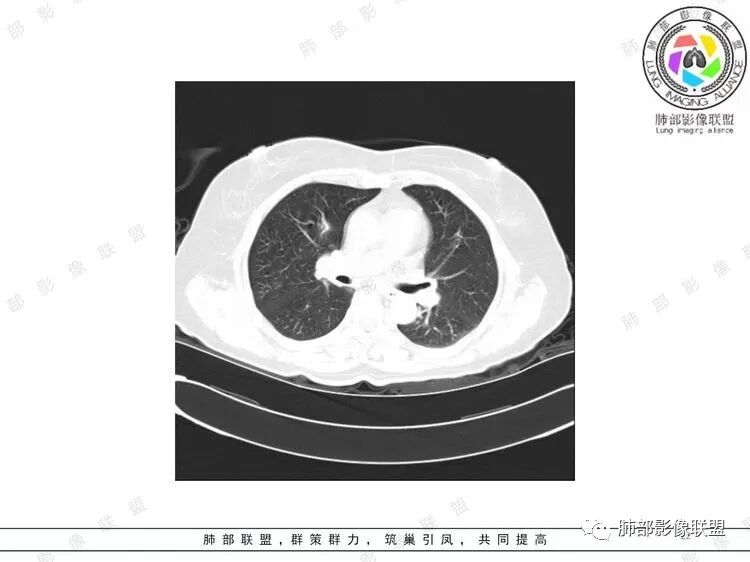

胸CT:双中下肺支气管壁明显增厚,双下肺胸膜下可见实变区。部分病变呈楔形影。

双肺多发大小不等结节,周围伴有晕征,边界模糊,部分结节内似可见支气管影,双肺血管束明显比支气管增粗,临床有感染症状,考虑GPA,疱疹病毒。

双肺支气管管壁弥漫性增厚,管腔狭窄,下叶为主,伴多发高密度结节影,边缘模糊,双肺支气管血管束明显增粗,临床症状咳嗽低热,有血尿,首先考虑血管炎

影像上:多发结节沿血管分布;双下叶支气管血管束简直增厚,偏血管,支气管通畅

首先肺部气道来源的病变不符合

因为支气管壁增厚,远端应该小气道病变,这个不是,反而是血管增粗明显